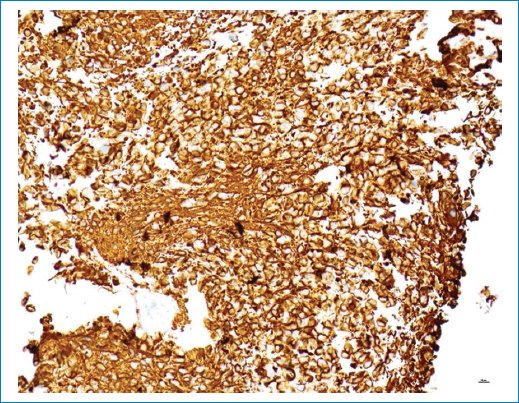

La biopsia mostró una neoplasia infiltrante hipercelular compuesta por pequeñas células “azules” con núcleos redondos hipercromáticos y escaso citoplasma o, de forma más focal, por células fibrilares con núcleos hipercromáticos alargados (Fig. 7). El tumor mostró una actividad mitótica muy alta, con hasta 16 figuras mitóticas por campo de alta potencia (Fig. 8). La IHQ con anticuerpo Ki-67 mostró un índice de proliferación Ki-67 muy alto, hasta del 56%, en correlación con la actividad mitótica elevada (Fig. 9). El origen glial del tumor se estableció por IHQ con el marcador glial GFAP que mostró una tinción fuerte y difusa del citoplasma de la célula tumoral (Fig. 10), mientras que un carcinoma de mama metastásico fue descartado por IHC con anticuerpos keratin CAM 5.2 y GCDFP-15. El anticuerpo p53 mostró una regulación positiva en algunos núcleos de células tumorales dispersos, lo que no sugiere una mutación TP53. Por el contrario, la IHQ con un anticuerpo específico para la mutación histona H3 K27M mostró una expresión fuerte y difusa de la proteína mutante en los núcleos de las células tumorales, pero no en los núcleos no tumorales de la vasculatura (Fig. 11). Este resultado estableció el diagnóstico final de este tumor como glioma difuso de línea media, mutante de histona H3 K27M (DMG/K27M), grado 4 de la OMS.

Figura 11. La mutación de la histona H3 K27M se detectó únicamente en las células tumorales. La presencia de la mutación se detectó mediante inmunohistoquímica con un anticuerpo específico para la mutación. Obsérvese la fuerte expresión nuclear en todas las células tumorales y la ausencia de expresión en las células vasculares no tumorales. Aumento de la imagen: 20x.